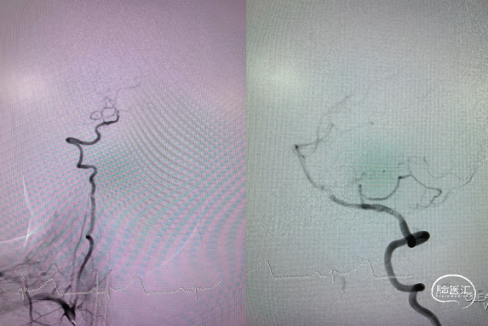

病变部位造影:

3、左侧股动脉穿刺,5F导引导管上高至左侧颈内动脉C1段,微导丝引导Echelon™ 10微导管头端超选入动脉瘤瘤腔内,依次填入部分弹簧圈。先行填入几枚弹簧圈有助于在Pipeline™ Flex 血流导向密网支架释放过程中,一定程度上保持Echelon™ 10微导管头端的稳定性,减少栓塞微导管移位。

4、经Marksman™ 微导管输送Pipeline™ Flex 血流导向密网支架 375-35,准确输送到位后,开始释放Pipeline™ Flex 血流导向密网支架。